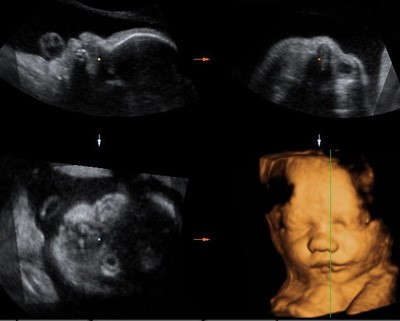

Лицо плода в 3-х проекциях в режиме 2D и его трехмерная (3D) реконструкция

3D (3Д) УЗИ – это способ получения изображения, которое достигается путем сложного преобразования полученной двухмерной информации в трехмерную объемную модель. Преобразования выполняются при помощи специального трехмерного датчика и компьютерных программ, входящих в состав ультразвукового аппарата. Полученные объемы можно поворачивать и рассматривать с различных сторон.

4D(4Д) УЗИ – это получение трехмерного изображения плода и его движений в реальном времени. Таким образом, помимо объемного изображения плода добавляется четвертое измерение – время, и можно рассматривать двигательную активность и мимику плода в движении.